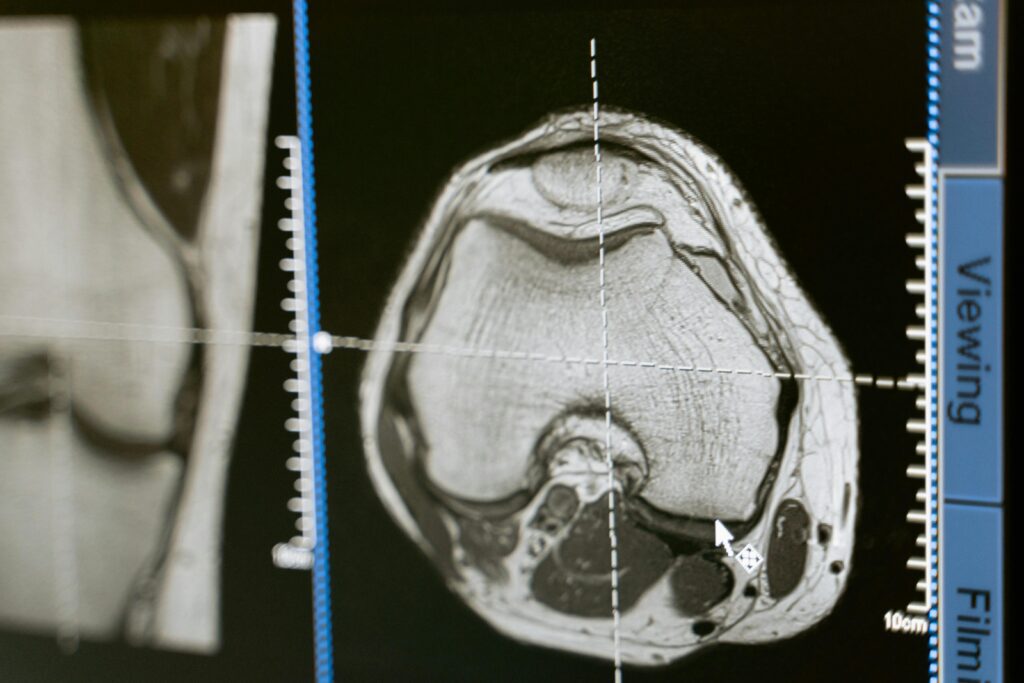

Rezonans magnetyczny (MRI) jest jedną z najbardziej zaawansowanych metod diagnostyki obrazowej, wykorzystującą silne pole magnetyczne do uzyskania obrazów o wysokiej rozdzielczości. Dzięki temu możliwa jest szczegółowa ocena mózgu, stawów, serca czy narządów jamy brzusznej.

W dziedzinach takich jak neurologia, ortopedia, kardiologia czy onkologia MRI stanowi standard diagnostyczny w wielu jednostkach chorobowych. Publikacje naukowe podkreślają jego przewagę nad innymi metodami w ocenie tkanek miękkich oraz zmian zapalnych i nowotworowych.

- Ocena urazów i chorób narządu ruchu